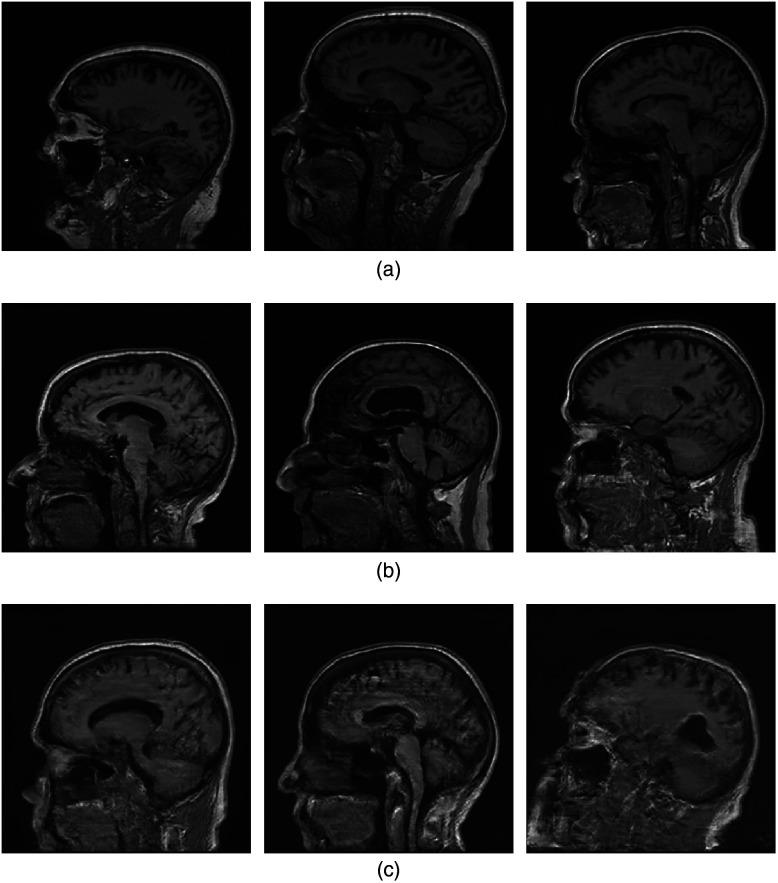

To objectively assess new medical imaging technologies via computer-simulations, it is important to account for the variability in the ensemble of objects to be imaged. This source of variability can be described by stochastic object models (SOMs). It is generally desirable to establish SOMs from experimental imaging measurements acquired by use of a well-characterized imaging system, but this task has remained challenging. A generative adversarial network (GAN)-based method that employs AmbientGANs with modern progressive or multiresolution training approaches is proposed. AmbientGANs established using the proposed training procedure are systematically validated in a controlled way using computer-simulated magnetic resonance imaging (MRI) data corresponding to a stylized imaging system. Emulated single-coil experimental MRI data are also employed to demonstrate the methods under less stylized conditions. The proposed AmbientGAN method can generate clean images when the imaging measurements are contaminated by measurement noise. When the imaging measurement data are incomplete, the proposed AmbientGAN can reliably learn the distribution of the measurement components of the objects. Both visual examinations and quantitative analyses, including task-specific validations using the Hotelling observer, demonstrated that the proposed AmbientGAN method holds promise to establish realistic SOMs from imaging measurements.

为了通过计算机模拟客观评估新的医学成像技术,考虑待成像物体集合中的变异性很重要。这种变异性来源可以用随机物体模型(SOM)来描述。通常希望从使用特征明确的成像系统获取的实验成像测量中建立SOM,但这项任务仍然具有挑战性。提出了一种基于生成对抗网络(GAN)的方法,该方法采用具有现代渐进式或多分辨率训练方法的环境GAN。使用所提出的训练过程建立的环境GAN使用对应于程式化成像系统的计算机模拟磁共振成像(MRI)数据以可控方式进行系统验证。还采用模拟的单线圈实验MRI数据来证明该方法在不太程式化的条件下的有效性。当成像测量受到测量噪声污染时,所提出的环境GAN方法可以生成清晰的图像。当成像测量数据不完整时,所提出的环境GAN可以可靠地学习物体测量分量的分布。视觉检查和定量分析,包括使用霍特林观察者进行的特定任务验证,都表明所提出的环境GAN方法有望从成像测量中建立逼真的SOM。